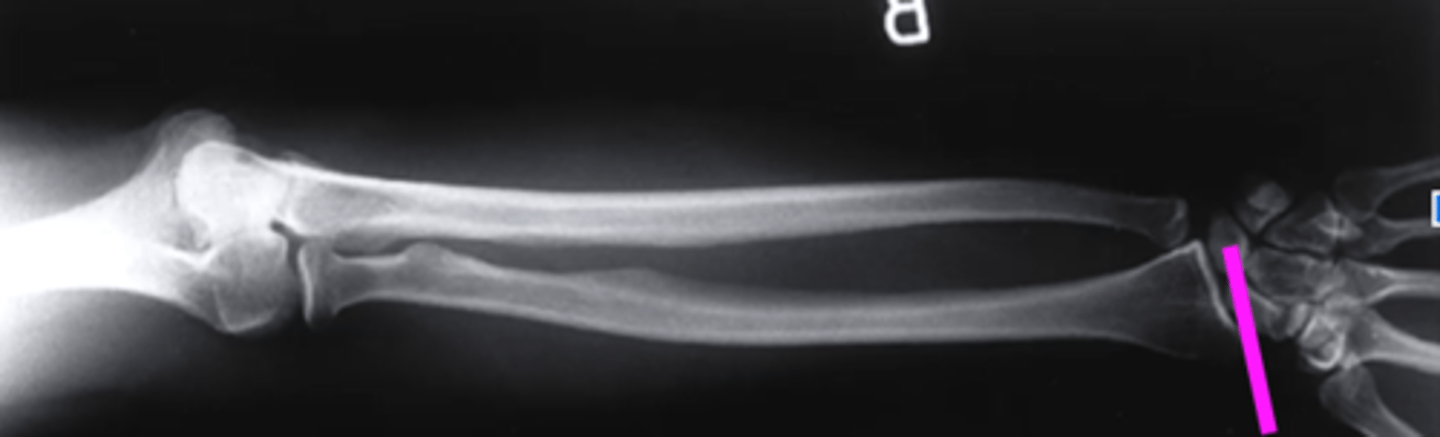

AP forearm

what view is this?

olecranon process

what does this pink line point to?

trochlea

capitulum

humeroradial joint

proximal radioulnar joint

radial tuberosity

radial styloid

distal radioulnar joint

scaphoid

lunate